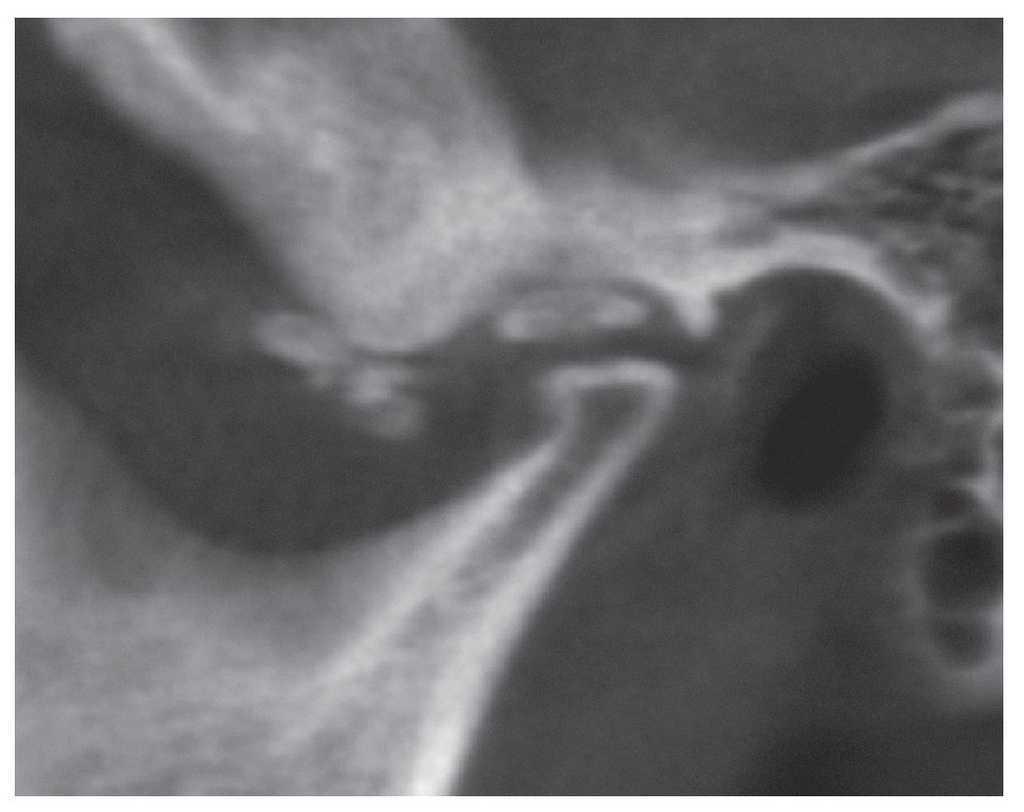

Para una valoración más detallada de las relaciones anatómicas y de las dimensiones de la calcificación se practicó una tomografía volumétrica digital dental. Se observaron múltiples calcificaciones de pequeño tamaño en la parte anterior y media del cóndilo articular (figs. 2 y 3). Se constató una calcificación de mayor tamaño directamente encima del cóndilo. Al mismo tiempo llama la atención un ensanchamiento marcado de la base craneal (fig. 4). Este hallazgo sugiere una posible etiología inflamatoria de las calcificaciones. En pacientes muy jóvenes hay que tener presente la posibilidad de una artritis reumatoide, si bien en el caso que nos ocupa la ausencia de sintomatología clínica iría en contra de este diagnóstico. La falta de síntomas es más bien una característica de la condromatosis sinovial. Esta enfermedad rara que se acompaña de la formación de encondromas aislados, los cuales se calcifican posteriormente, no suele provocar dolor en la articulación temporomandibular hasta fases avanzadas. Es posible observar encondromas libres en el espacio articular. En estos casos hay que hacer el diagnóstico diferencial con una osteocondrosis disecante (OCD).

Figura 2. Tomografía volumétrica digital dental: plano sagital.